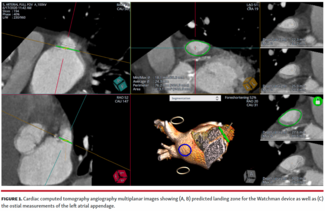

A prospective analysis of 71 non-consecutive patients who underwent LAAO over an 18-month period with cardiac CTA-guided preprocedural planning and ICE was conducted.